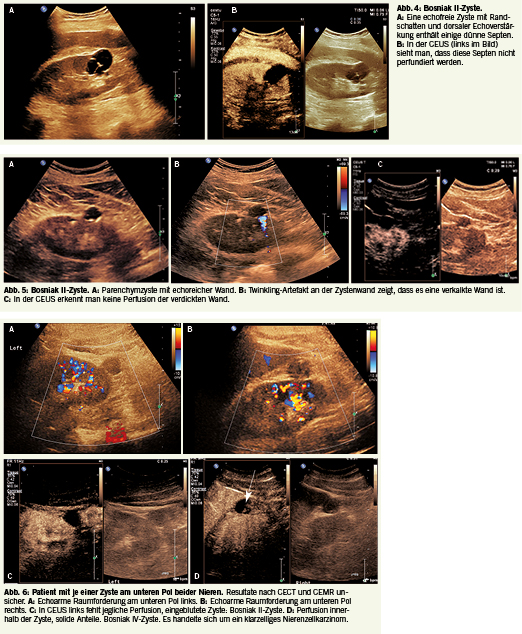

Charakteristika Bosniak II komplexe Zyste:

• Wand dünn, leicht verdickt

(2-3 mm und oder verkalkt

• Septen 1-3, <2 mm dünn, kaum perfundiert

•Zysteninhalt

echofrei, oder homo- gen oder gemischt echogen

• Kontrastierung minim

• Solide Anteile keine

Die Einteilung der komplexen Zysten erfordert immer eine Bildgebung mit Kontrastverstärkung (CECT, CEMR, CEUS). Ultraschall hat hier viele Vorteile: hohe Sensitivität, gute örtliche Auflösung und dass der Einsatz von ionisierenden Strahlen oder nephrotoxischen Substanzen vermieden werden kann. Daher ist es von Vorteil, als erste Untersuchung bei komplizierten Zysten eine CEUS durchzuführen. Die Bosniak II Zyste ist entweder septiert, mit sehr dünnen Septen (Abb. 4a-b) oder die Zyste hat eine verdickte und oder verkalkte Wand, die nicht oder kaum perfundiert ist (Abb. 5a-c). Diese Zysten sind gutartig und brauchen daher prinzipiell keine Nachkontrollen. Zysten mit Einblutungen haben einen echogenen Zysteninhalt im B-Bild. In diesen Fällen ist die Untersuchung mit CEUS besonders wichtig, da die örtliche Auflösung dieser Methode besser ist als CECT oder CEMR. Die beim Ultraschall eingesetzten Kontrastmittel sind Gasblasen, die etwas kleiner als Erythrozyten sind und somit strikt intravaskulär bleiben, währenddessen bei CT und MR als Kontrastmittel kleinmolekulare Stoffe verwendet werden, welche aus den Gefässen diffundieren, so dass dabei auch Anteile, die nicht durchblutet sind fälschlicherweise als perfundierte Strukturen beurteilt werden. Bei kleinen homogen echogenen Zysten ist die CEUS deshalb sehr wichtig, wie der folgende Fall illustriert: Ein Patient hatte beidseits je eine echogene Zyste. Die Situation war im CEMR und CECT unsicher, weshalb eine CEUS folgte. Dabei konnte eine Zyste links als harmlose eingeblutete Zyste, die rechte jedoch als Nierenzellkarzinom diagnostiziert werden (Abb. 6 a-d).